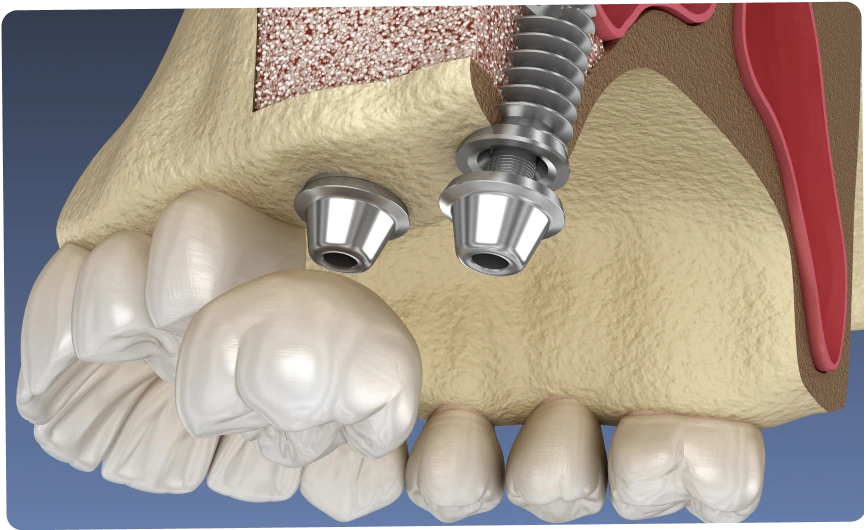

La greffe de sinus, aussi appelée élévation sinusienne, est une intervention chirurgicale en odontologie visant à augmenter la quantité d’os disponible dans la partie postérieure de la mâchoire supérieure. Cette zone, située sous les sinus maxillaires, peut parfois présenter un volume osseux insuffisant pour accueillir un implant dentaire. La greffe permet alors de créer un support solide et durable pour assurer la stabilité d’une future prothèse implantaire.

Il existe deux grandes approches de la greffe de sinus, choisies en fonction de la quantité d’os disponible et de la complexité du cas.

Cette technique est utilisée lorsque la hauteur osseuse est très limitée. Le praticien accède au sinus par une petite fenêtre réalisée sur le côté de la gencive. La membrane sinusienne est alors délicatement soulevée, et l’espace créé est comblé par un matériau de greffe osseuse. Après une période de cicatrisation, il sera possible de poser les implants.

Moins invasive, cette méthode s’applique lorsque la perte osseuse est modérée. Le praticien accède au sinus par l’emplacement même prévu pour l’implant. L’élévation est réalisée progressivement et un matériau de comblement peut être ajouté. Dans certains cas, l’implant peut être posé dans la même séance.

Ces techniques, bien que différentes, poursuivent le même objectif : recréer un volume osseux suffisant pour assurer la stabilité d’implants durables.